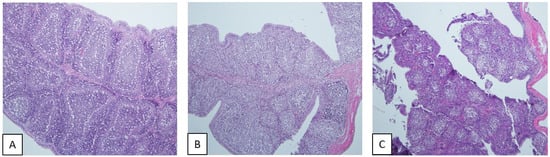

3.5. Comparative Pathogenicity Study of IBDV Strains Belonging to Different G2 Subgroups